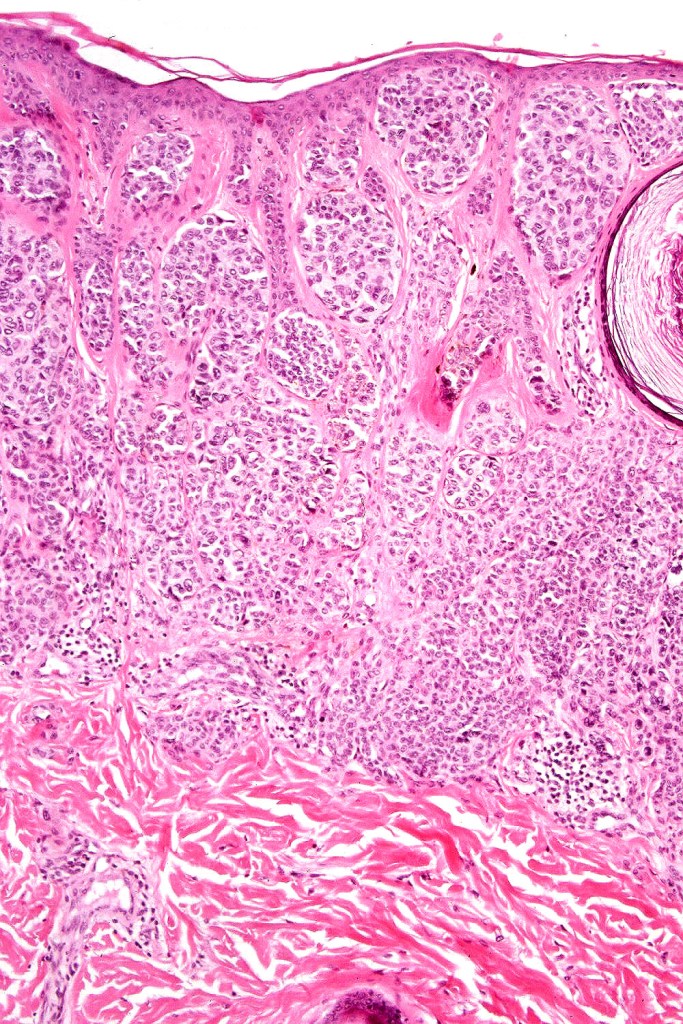

Histological features

•Most often are distinctive at scanning/low power examination due to the depth of involvement

•Hyperkeratosis, acanthosis and commonly papillomatosis

•Nested junctional component & nests within the papillary dermis

•Diffuse infiltrate of nevus cells often extending deeply into the dermis or beyond, single filing is often present at base & may involve the septa of the subcutaneous fat

•Involvement of appendages & arrector pili muscles